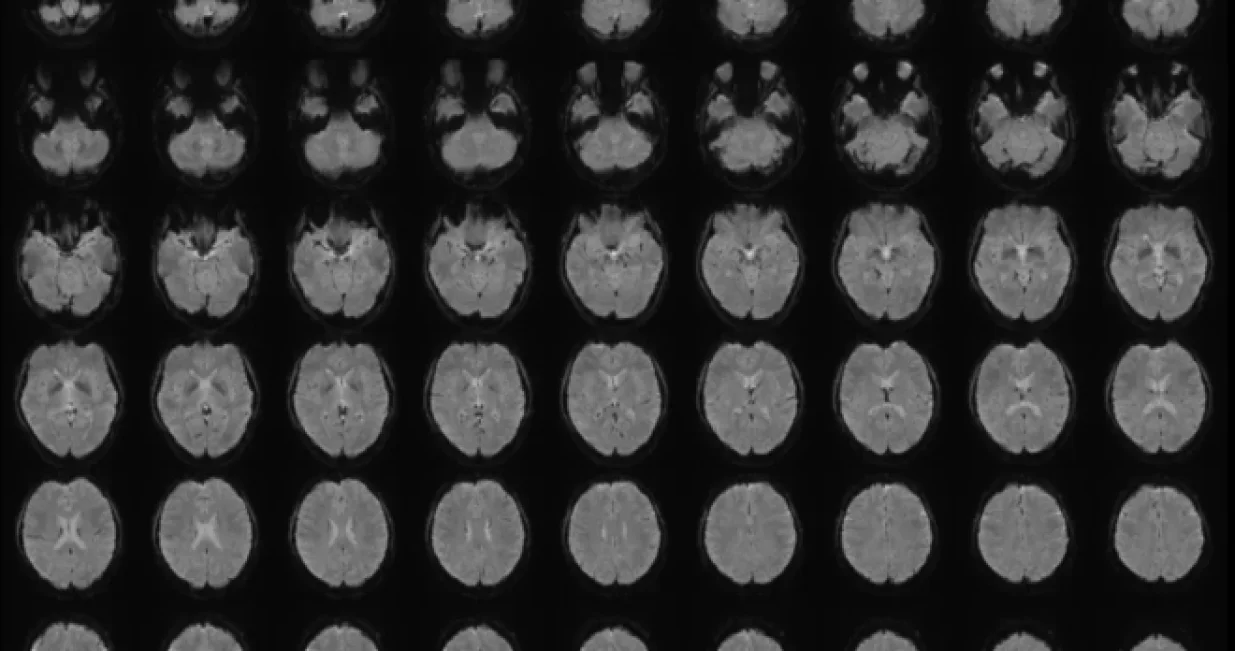

U osnovi metode nalazi se vještačka inteligencija obučena na tekstualnim opisima više od 2.000 videa. Svaki opis pretvoren je u numerički semantički potpis, odnosno digitalni zapis značenja rečenice. Paralelno s tim, istraživači su koristili funkcionalne MRI skenere kako bi snimili moždanu aktivnost šest učesnika dok su gledali iste te videe. AI je naučila da povezuje obrasce moždane aktivnosti s pripadajućim semantičkim potpisima.